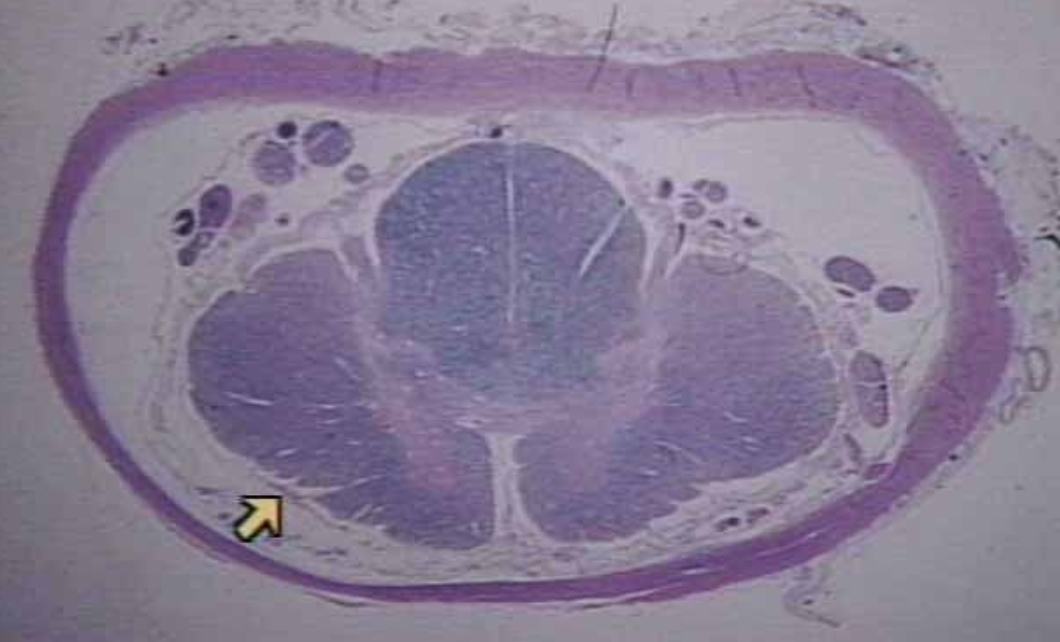

What is this

Midsagittal section of cerebellum (Microscopic real view)

A

Dura Mater (Microscopic Real View)

B

Gray Mater (Microscopic Real View)

C

White Mater (Microscopic Real View)